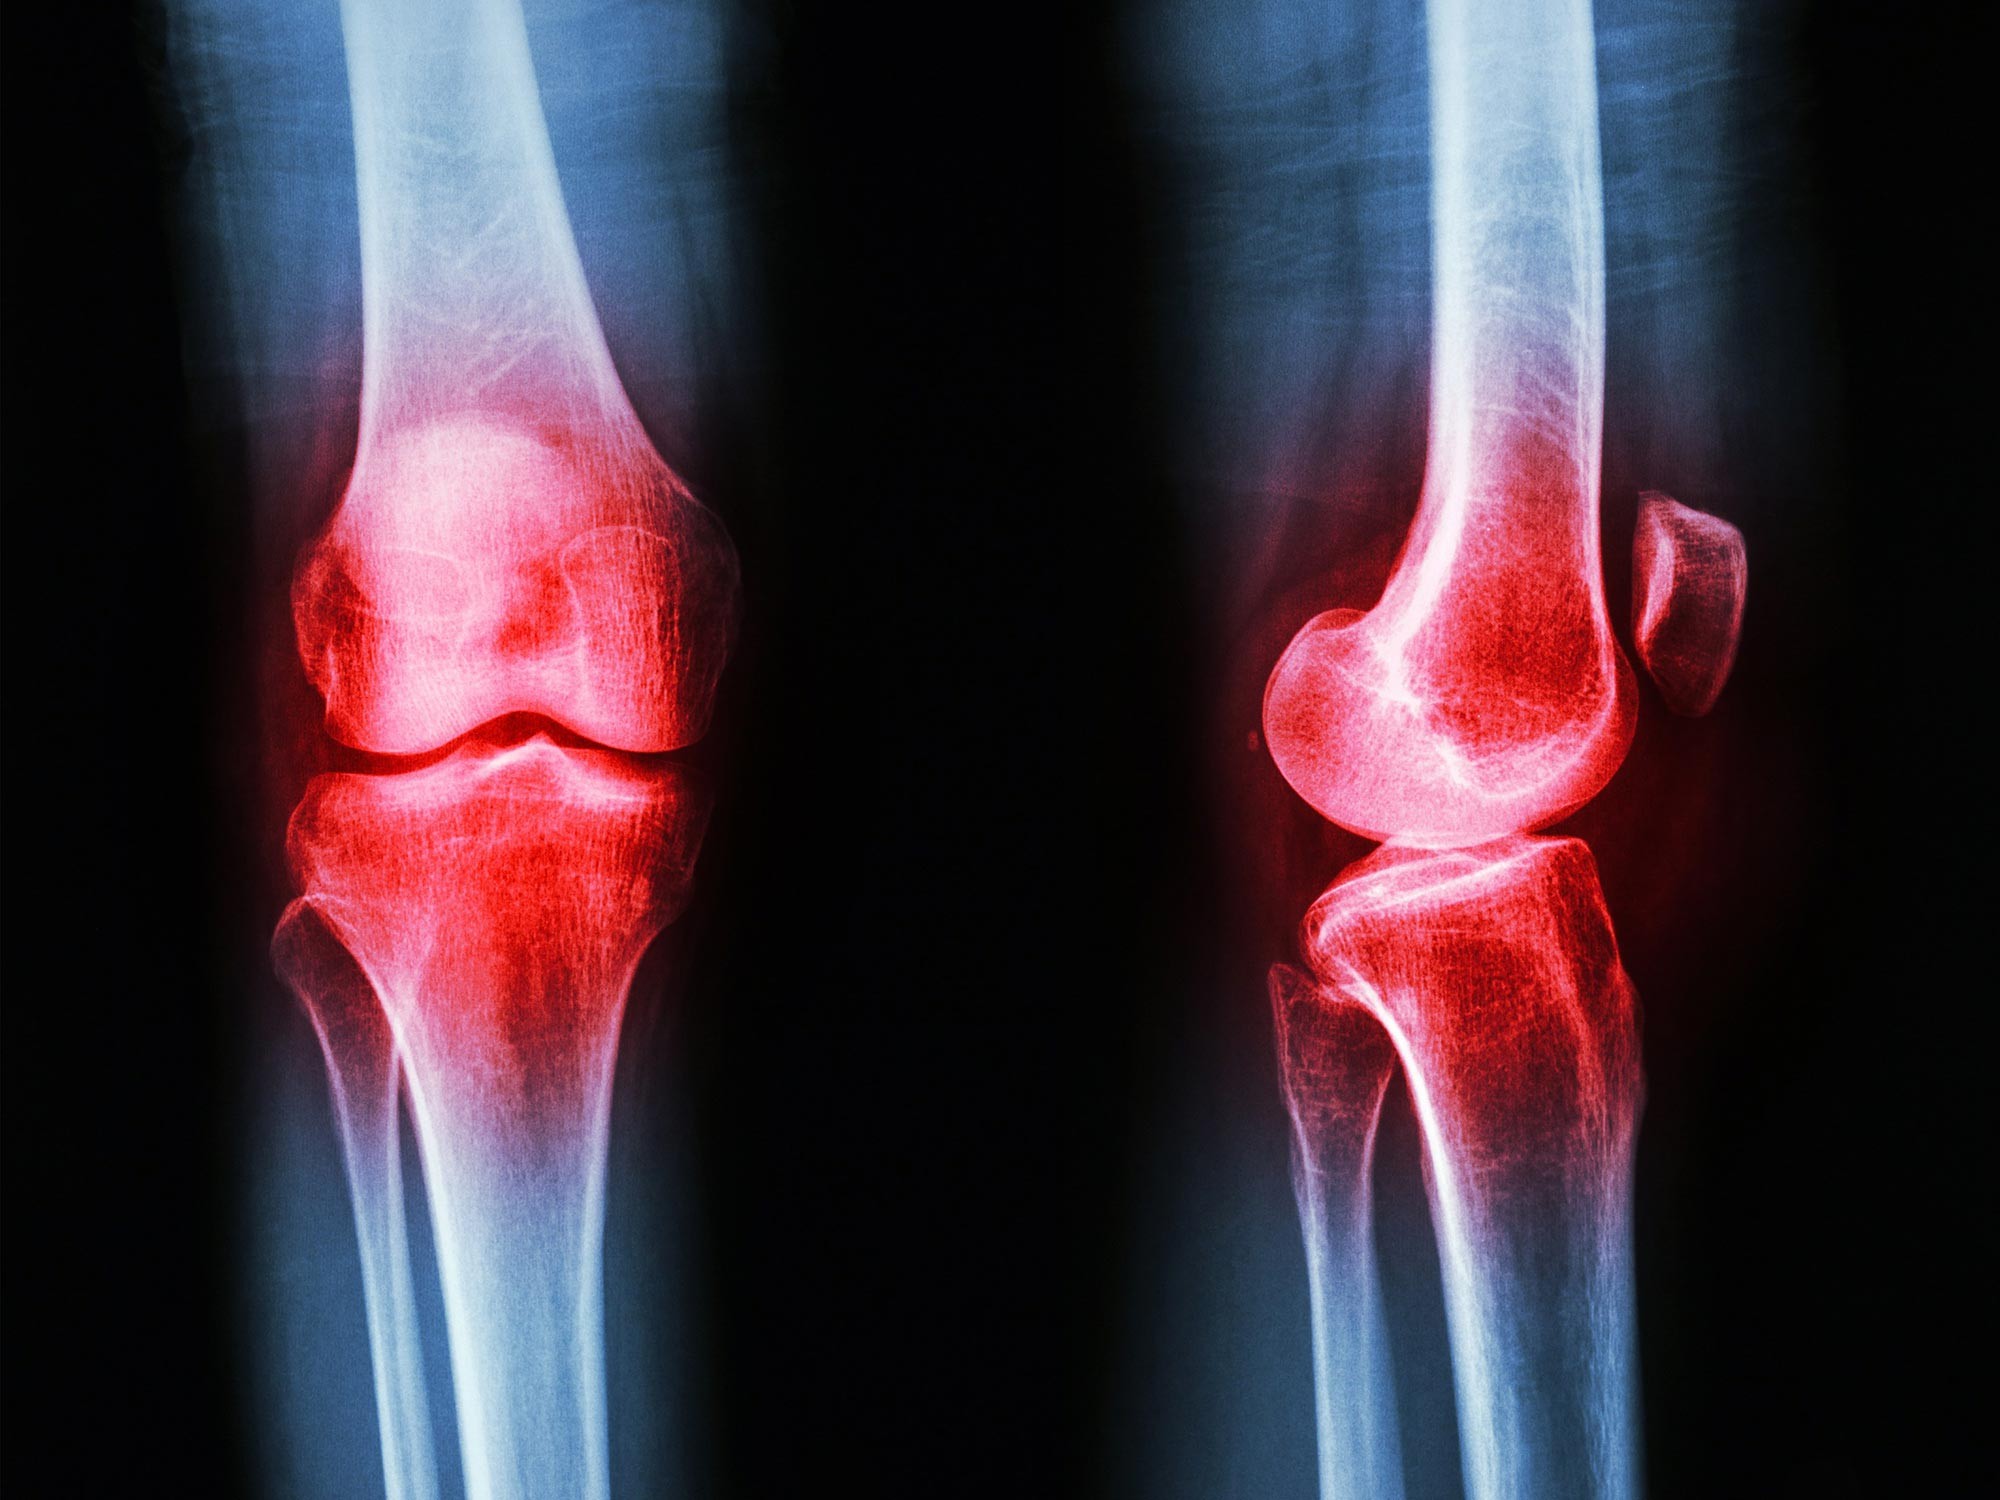

Артрит — це широкий термін, що охоплює різні стани: від дегенеративного остеоартриту до аутоімунних захворювань, таких як ревматоїдний артрит. Незважаючи на відмінності в походженні, у всіх цих станів є спільний ворог: хронічне запалення, яке призводить до болю, скутості та втрати рухливості.

Традиційно методи лікування артриту спрямовані на усунення цих симптомів або придушення імунної системи. Однак дослідження, опубліковане в журналі The Lancet Rheumatology, передбачає, що гормон GLP-1 може відігравати несподівану роль у середовищі суглобів.